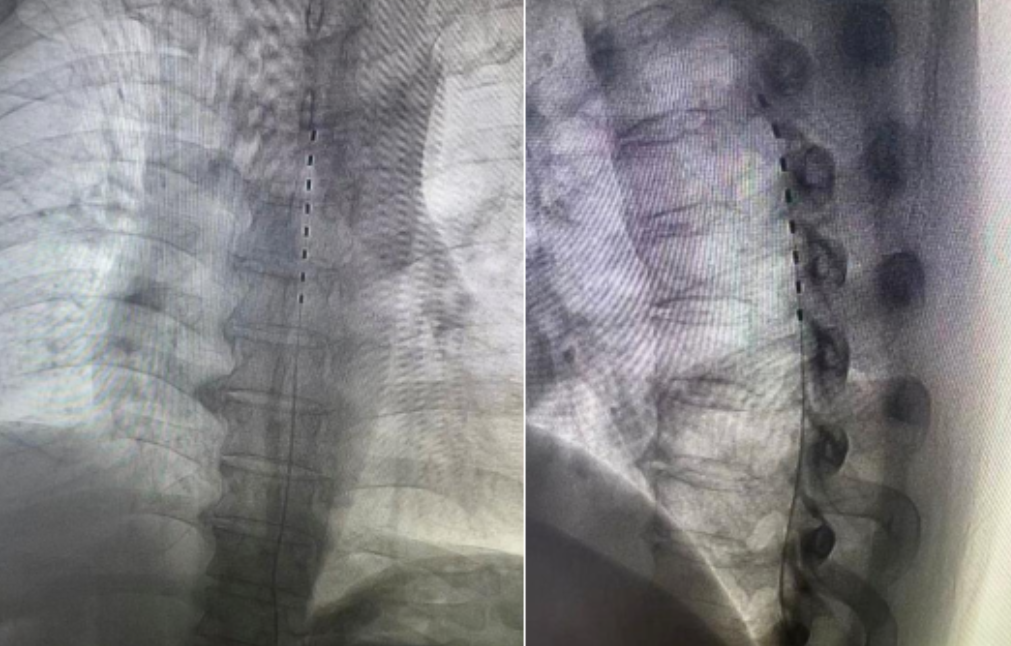

手术采取局麻方式,术中患者保持清醒,并积极配合调试电极,确保电极范围完全覆盖疼痛部位。凭借扎实的基础和精湛的技术,不到1个小时,手术便顺利完成。术后,患者疼痛就减轻了。

带状疱疹后神经痛属于严重的神经病理性疼痛。脊髓电刺激通过穿刺,将电极短期植入到硬膜外或周围神经附近,由体外脉冲发生器发放持续电脉冲,通过刺激脊髓背柱、脊神经根、背根神经节或周围神经,调节神经系统功能达到缓解疼痛的目的,是一种方便、可逆性的纯物理的微创治疗方法。